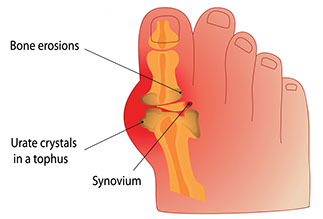

Gout

Signs & Symptoms

Sudden, severe pain in a toe, knee, or ankle joint. The pain can be felt even when clothing is rubbed against the joint. The joint area is swollen, red, or purplish in color. It also feels warm, and is very tender to the touch.